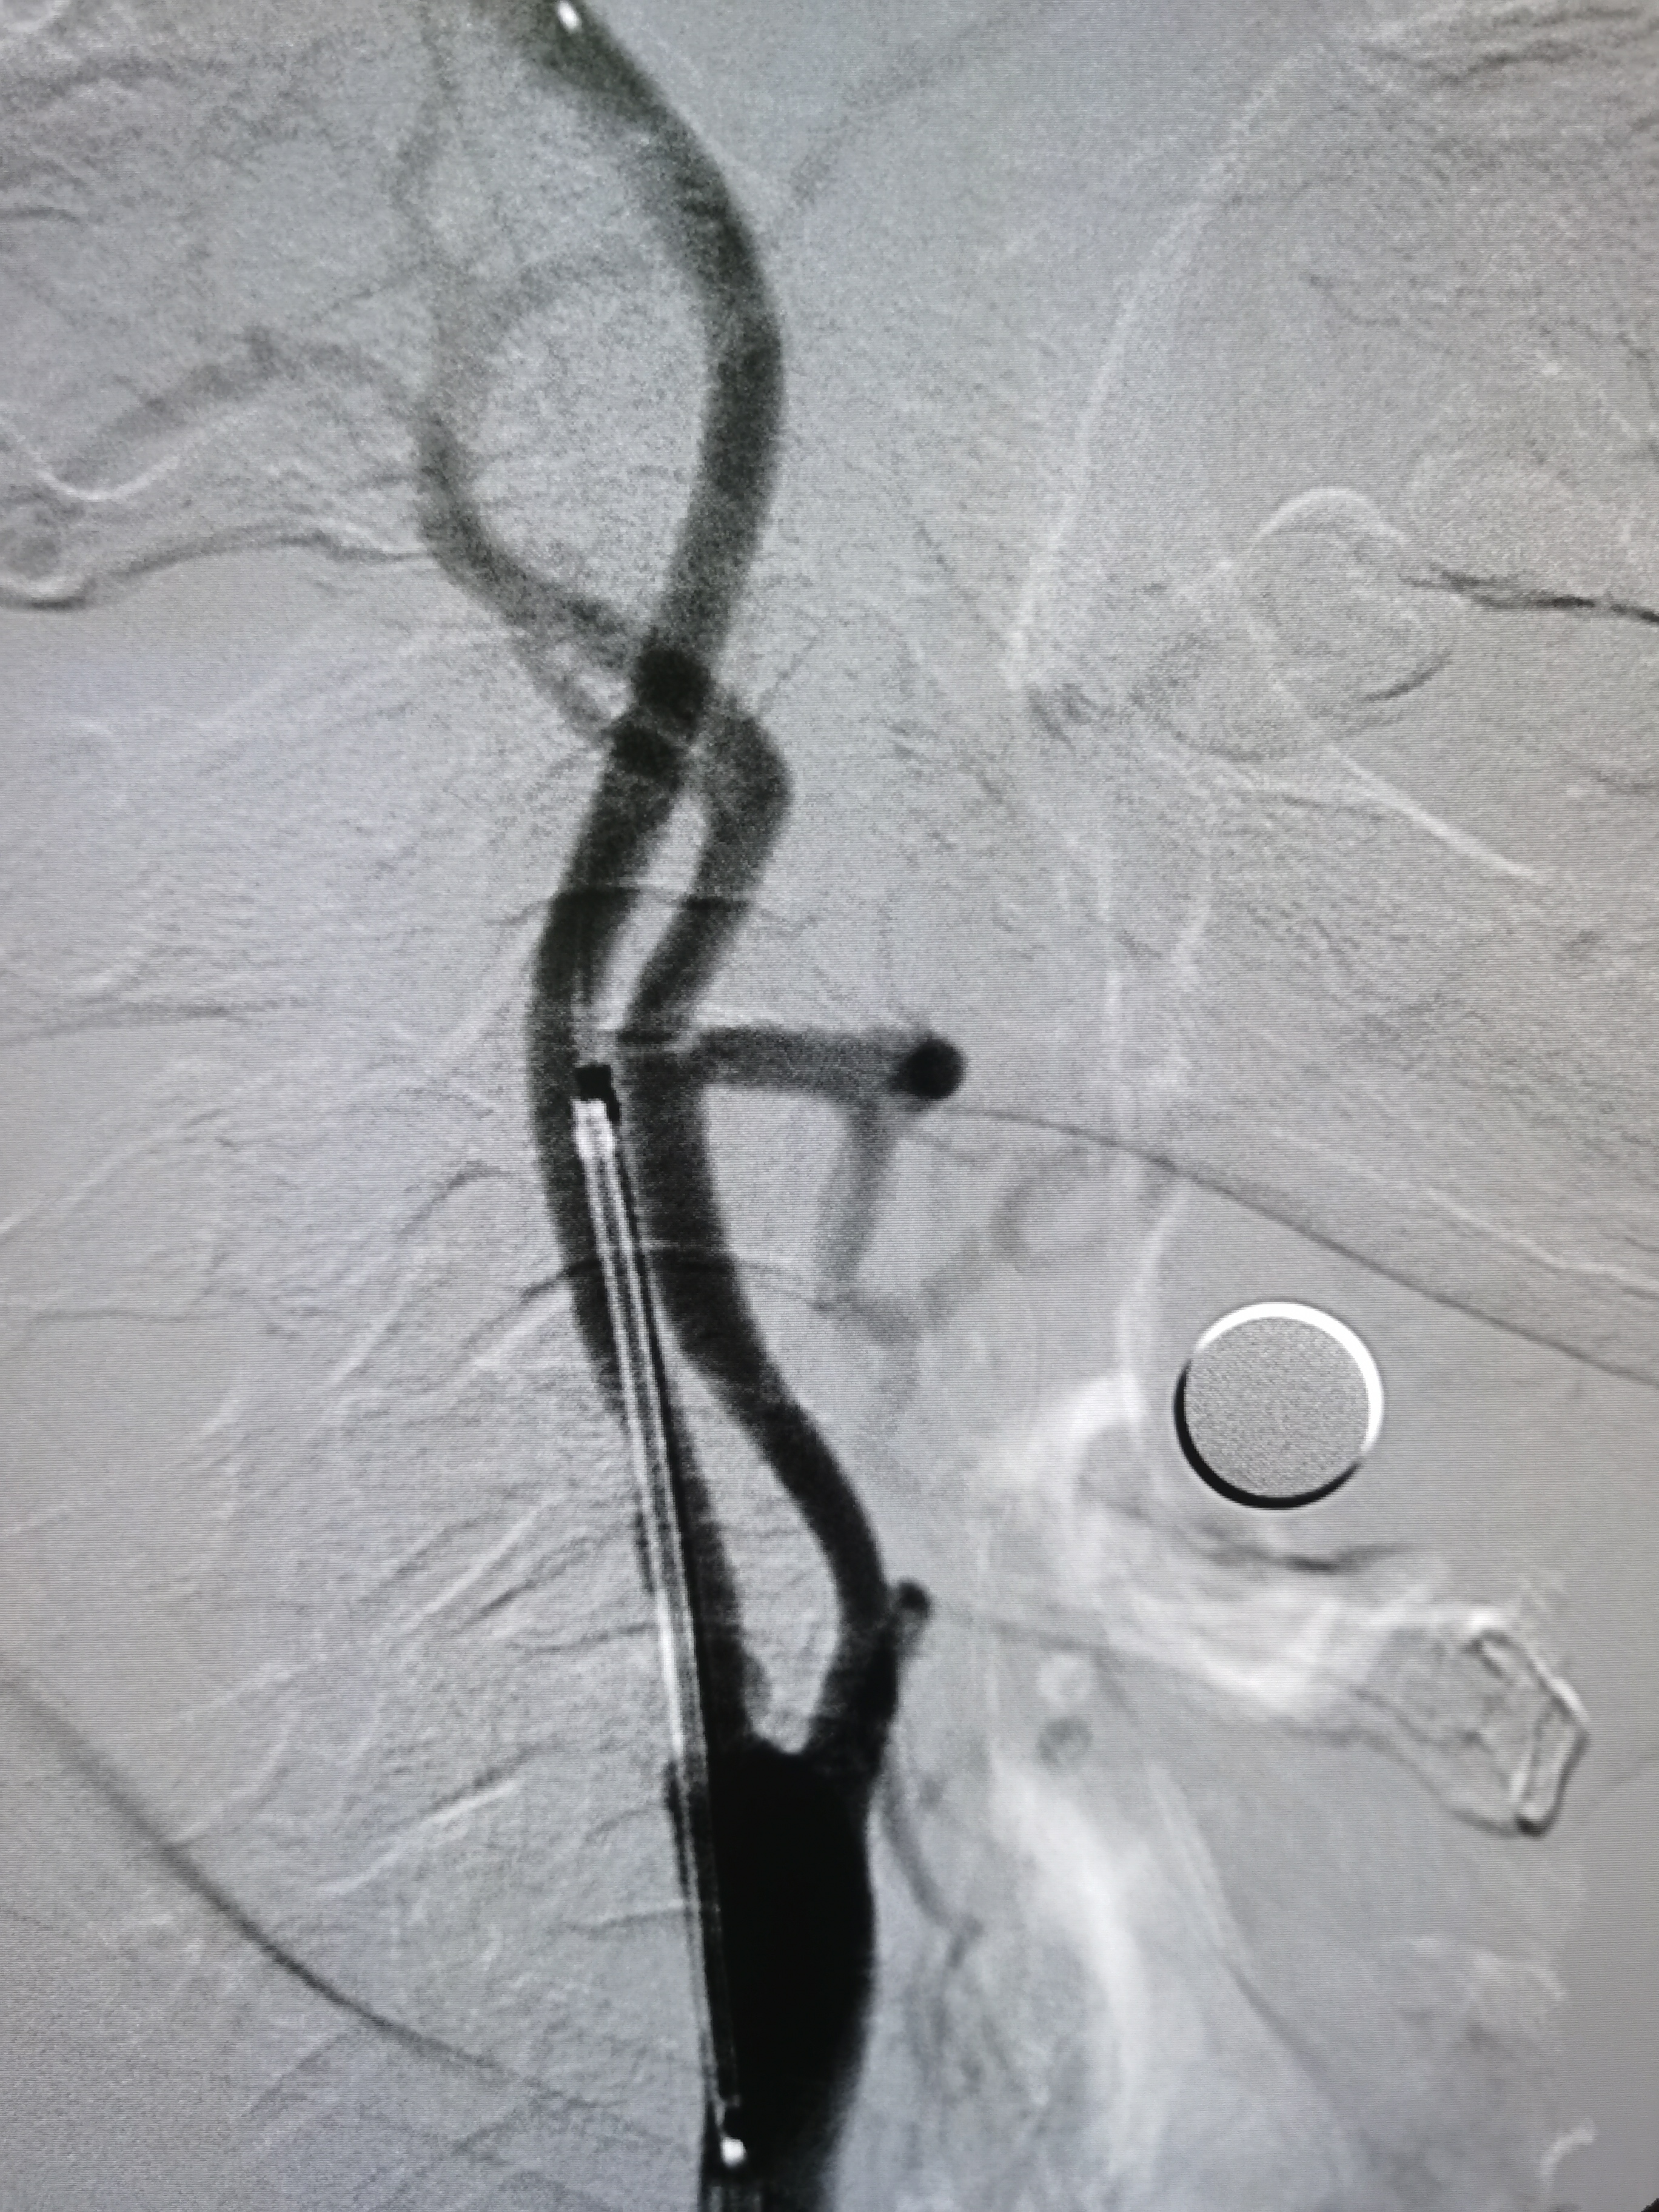

8F导引导管到位右侧颈总动脉末端,明确狭窄。

微导丝顺利通过病变,交换入远端保护伞。

2/20,4/30球囊渐进性预扩后狭窄改善。

9/30支架定位后释放。

支架释放后狭窄解除。

支架释放后颅内血供改善。